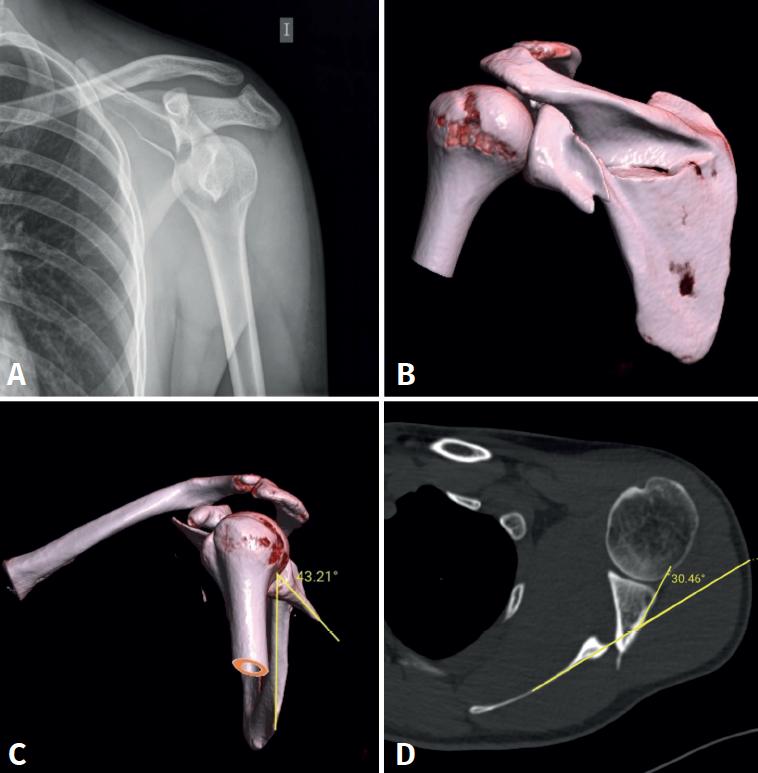

A la exploración física el paciente presenta un hematoma en la zona escapular izquierda con impotencia funcional para la movilización tanto activa como pasiva de la extremidad superior izquierda. Posteriormente, se completa el estudio de la lesión con radiografías simples y TC (Figura 1) que evidencian una fractura del cuello anatómico de la glenoides con presencia de un trazo horizontal en el cuerpo de la escápula y sin afectación intraarticular. El fragmento glenoideo presenta una rotación de 43° con una inclinación anterior de 30°; en cambio, el trazo a nivel del cuerpo de la escápula conserva una correcta alineación a pesar de su ligera conminución.